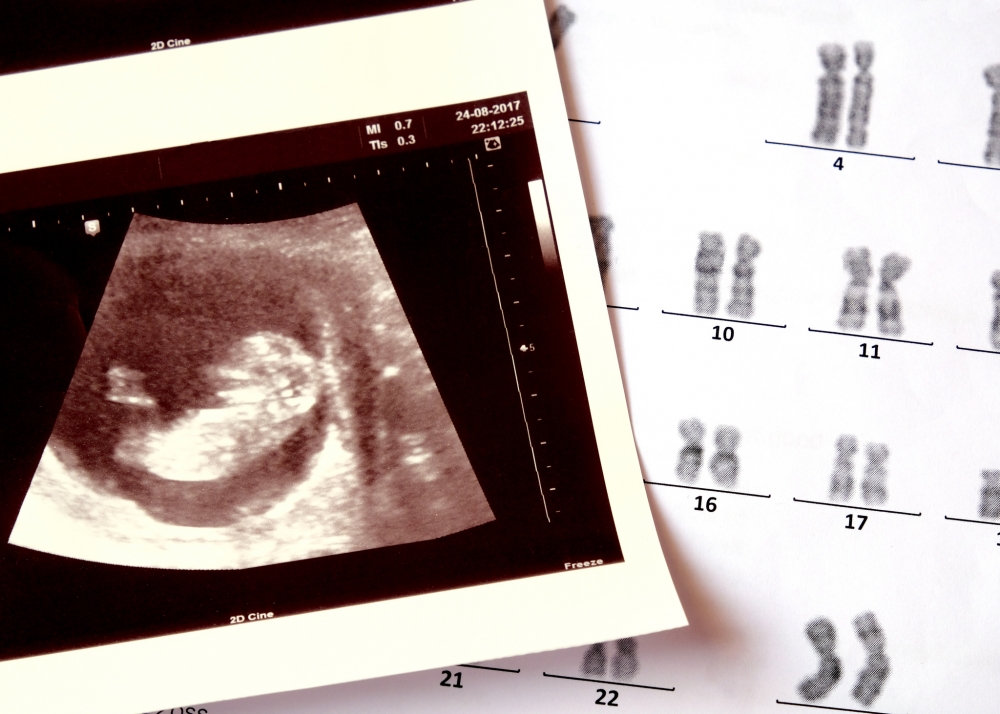

愛德華氏症也稱為18三染色體症(Edwards Syndrome,Trisomy 18),是指胚胎的第18號染色體出現3條染色體的異常情況,屬於遺傳基因疾病。當父親或母親的生殖細胞,在進行減數分裂形成精子或卵子時出現異常現象,便會出現精子或卵子的染色體數目異常,而愛德華氏症便是由第18號染色體異常造成。

由於目前醫學上無方法治療愛德華氏症,因此父母能做的就是及早檢測。懷孕初期(10-13週),醫院會定期為孕婦進行驗血、超聲波檢查、度量胎兒頸皮厚度等。通過檢測血液血清中的甲型胎兒蛋白(AFP)、絨毛膜性腺激素(hCG)、游離雌三醇(estriol)和抑制素-A (inhibin-A)等值,加上超聲波數據及胎兒頸皮厚度數值,判斷胎兒患上遺傳性疾病的概率。

有需要時,父母可選擇進行「無創DNA產前檢測」,抽血檢測孕婦血漿游離 DNA,檢測血漿內胎兒基因,可重點篩查三體綜合症,準確度高達99%。

若先前的篩查結果呈陽性,後續便需要進行絨毛膜取樣和羊膜穿刺檢查。兩項技術皆屬於侵入性檢查。絨毛膜取樣需從胎盤取得細胞樣本;羊膜穿刺檢查則是通過抽取子宮內羊膜腔的羊水來進行染色體檢測。